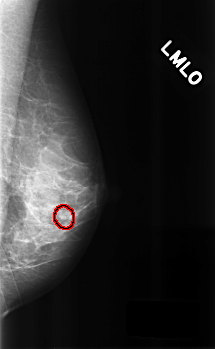

ics_version 1.0 filename C-0300-1 DATE_OF_STUDY 10 3 1995 PATIENT_AGE 38 FILM FILM_TYPE REGULAR DENSITY 3 DATE_DIGITIZED 5 8 1998 DIGITIZER LUMISYS LASER SEQUENCE LEFT_CC LINES 4560 PIXELS_PER_LINE 2776 BITS_PER_PIXEL 12 RESOLUTION 50 OVERLAY LEFT_MLO LINES 4528 PIXELS_PER_LINE 2792 BITS_PER_PIXEL 12 RESOLUTION 50 OVERLAY RIGHT_CC LINES 4632 PIXELS_PER_LINE 2928 BITS_PER_PIXEL 12 RESOLUTION 50 NON_OVERLAY RIGHT_MLO LINES 4648 PIXELS_PER_LINE 2896 BITS_PER_PIXEL 12 RESOLUTION 50 NON_OVERLAY |

FILE: C_0300_1.LEFT_MLO.OVERLAY TOTAL_ABNORMALITIES 1 ABNORMALITY 1 LESION_TYPE CALCIFICATION TYPE PLEOMORPHIC DISTRIBUTION CLUSTERED ASSESSMENT 4 SUBTLETY 3 PATHOLOGY BENIGN TOTAL_OUTLINES 1 BOUNDARY |